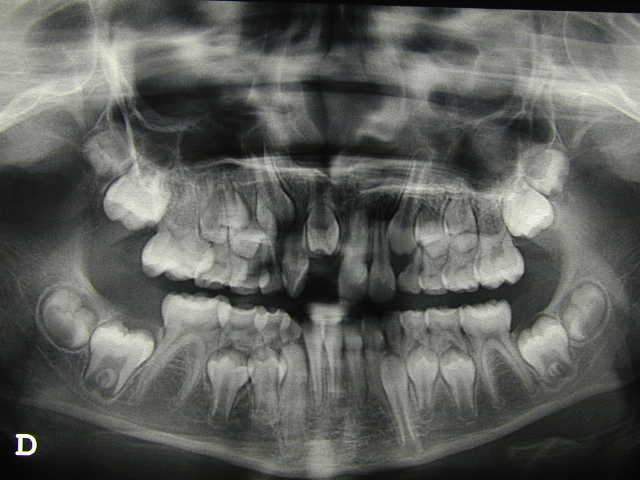

Lacand ayant des petits problemes de connexion internet, il m'a permis en son nom de diffuser les 3 images, qu'il vous commentera par la suite.